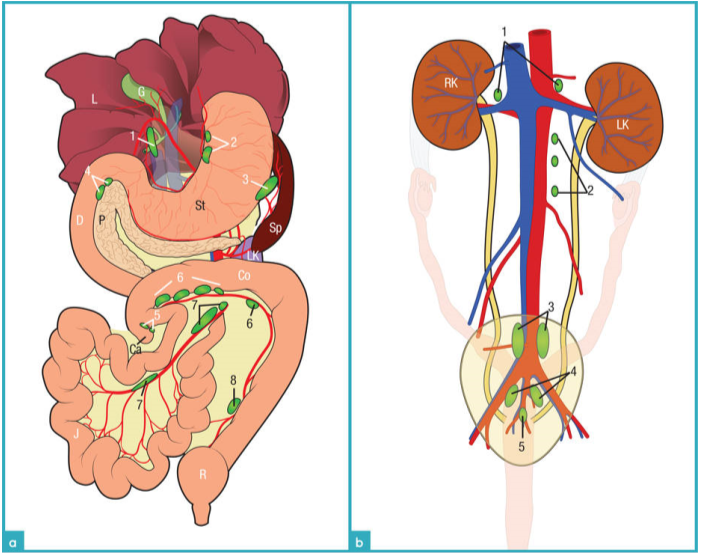

图5显示了猫腹部淋巴结的分布情况。淋巴结是根据脏层和壁层来划分的。四个壁层淋巴中心包括腰荐淋巴中心,髂骶淋巴中心,腹股沟淋巴中心,坐骨淋巴中心。三个脏层淋巴中心包括下腹淋巴中心,前肠系膜淋巴中心,后肠系膜淋巴中心。易见的脏层淋巴结有胃淋巴结,肝脏淋巴结,胰十二指肠淋巴结,空肠淋巴结,回盲淋巴结,结肠淋巴结(图6)。壁层淋巴结里易见的淋巴结包括有髂中淋巴结和腹股沟浅淋巴结(图7)脏层淋巴结中不易见的淋巴结包括有脾脏淋巴结和后肠系膜淋巴结(图8)。壁层淋巴结中不易见的淋巴结包括有腰动脉淋巴结,肾淋巴结,髂内淋巴结,骶骨淋巴结,尾部淋巴结,尾上腹淋巴结。浅表淋巴结例如腹股沟浅淋巴结和髂中淋巴结呈现细长的纺锤状。淋巴结的边缘规则,被膜产回声,它的实质相对于脂肪来讲是无回声的或是低回声的。腹部较深的淋巴结中只有空肠淋巴结,后肠系膜淋巴结是狭长的形状,其他的则为卵圆形。淋巴结的实质部分比脂肪组织的回声低,外周被脂肪组织包裹,清晰的边界。表1为腹部淋巴结的位置与大小。

腹部器官的血供是从主动脉的分支而来(下腹动脉,前肠系膜动脉,肾动脉,旋髂深动脉,髂外动脉,髂内动脉,骶中动脉)。腹腔的静脉血液有两个走向,一个走向是汇入后腔静脉,另一个走向是汇入门静脉。测量主动脉和CVC的血流速度时,需要使探头的切面与腰椎的长轴平行。腹主动脉从膈下行到第六腰椎的水平面,位置稍稍偏中线的左侧,是有高回声的管壁,内部是无回声的液体(图9a和9b),横截面上会更加清晰。二维扫查可以见到主动脉所有的分支。后腔静脉位于腹主动脉的右侧在超声形态上与腹主动脉相似。后腔静脉较腹主动脉而言,更容易被探头压扁(图9c)。门静脉位于肝门,它的分支有胃十二指肠静脉,脾静脉,前肠系膜静脉和后肠系膜静脉。门静脉位于腹中线偏右(图9d)。